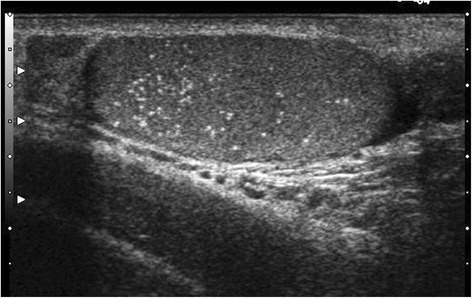

Testicular microlithiasis (TML) corresponds to concretions of hydroxyapatite surrounded by fibrosis located in the seminiferous tubes [1]. They are due to the insufficient capacity of Sertoli cells to phagocyte the degenerate cells present in these tubes. They are commonly discovered by ultrasound (US). They are not visible on Magnetic Resonance Imaging (MRI). In 1987, Doherty et al. [2] described their appearance on US, which is characterized by a hyperechoic focus measuring between 1 and 3 mm in the testicular parenchyma without posterior shadow cone [3] with a number greater than or equal to 5 per testis. The discovery is mostly fortuitous because there is no clinical manifestation. Their historical radiological classification is described by Backus et al. [4]. Three grades are distinguished according to the number of TML described by parenchyma (grade 1: 5 to 10, grade 2: 10 to 20 and grade 3 with more than 20 TML). In recent years, US has substantially improved with the advent of higher resolutions enhancing TML detection. In 2015, the European Society of Urogenital Radiology (ESUR) proposed a summary of guidelines and reported another classification with 3 groups, based on the number of TML per field of vision [5]. These three groups were defined as follows, limited TML: less than 5 per field of view (Fig. 1), classic TML: greater than or equal to 5 per field of view (Fig. 2) and finally diffuse TML, labelled “snowstorm” (Fig. 3). There are many observational studies on TML and testicular cancer risk. The objective was to perform a review of the available literature to date.

Fig. 2.

Classic testicular microlithiasis (TML): greater than or equal to 5 per field of view. With agreement from authors [8]